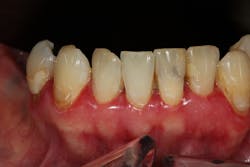

One reason people develop gummy smiles is inflammatory-induced gingival enlargement, typically caused by biofilm (bacteria) and the host response. Gum disease (gingivitis and periodontitis) can result in gum tissue swelling, redness, gum overgrowth, and bleeding (figure 1). In addition to bacterial infiltration of the gums due to poor oral hygiene, orthodontic appliances have been associated with gingival enlargement since braces can act as food traps (figure 2).Further reading: Considerations when using veneers to fabricate a perfect smile